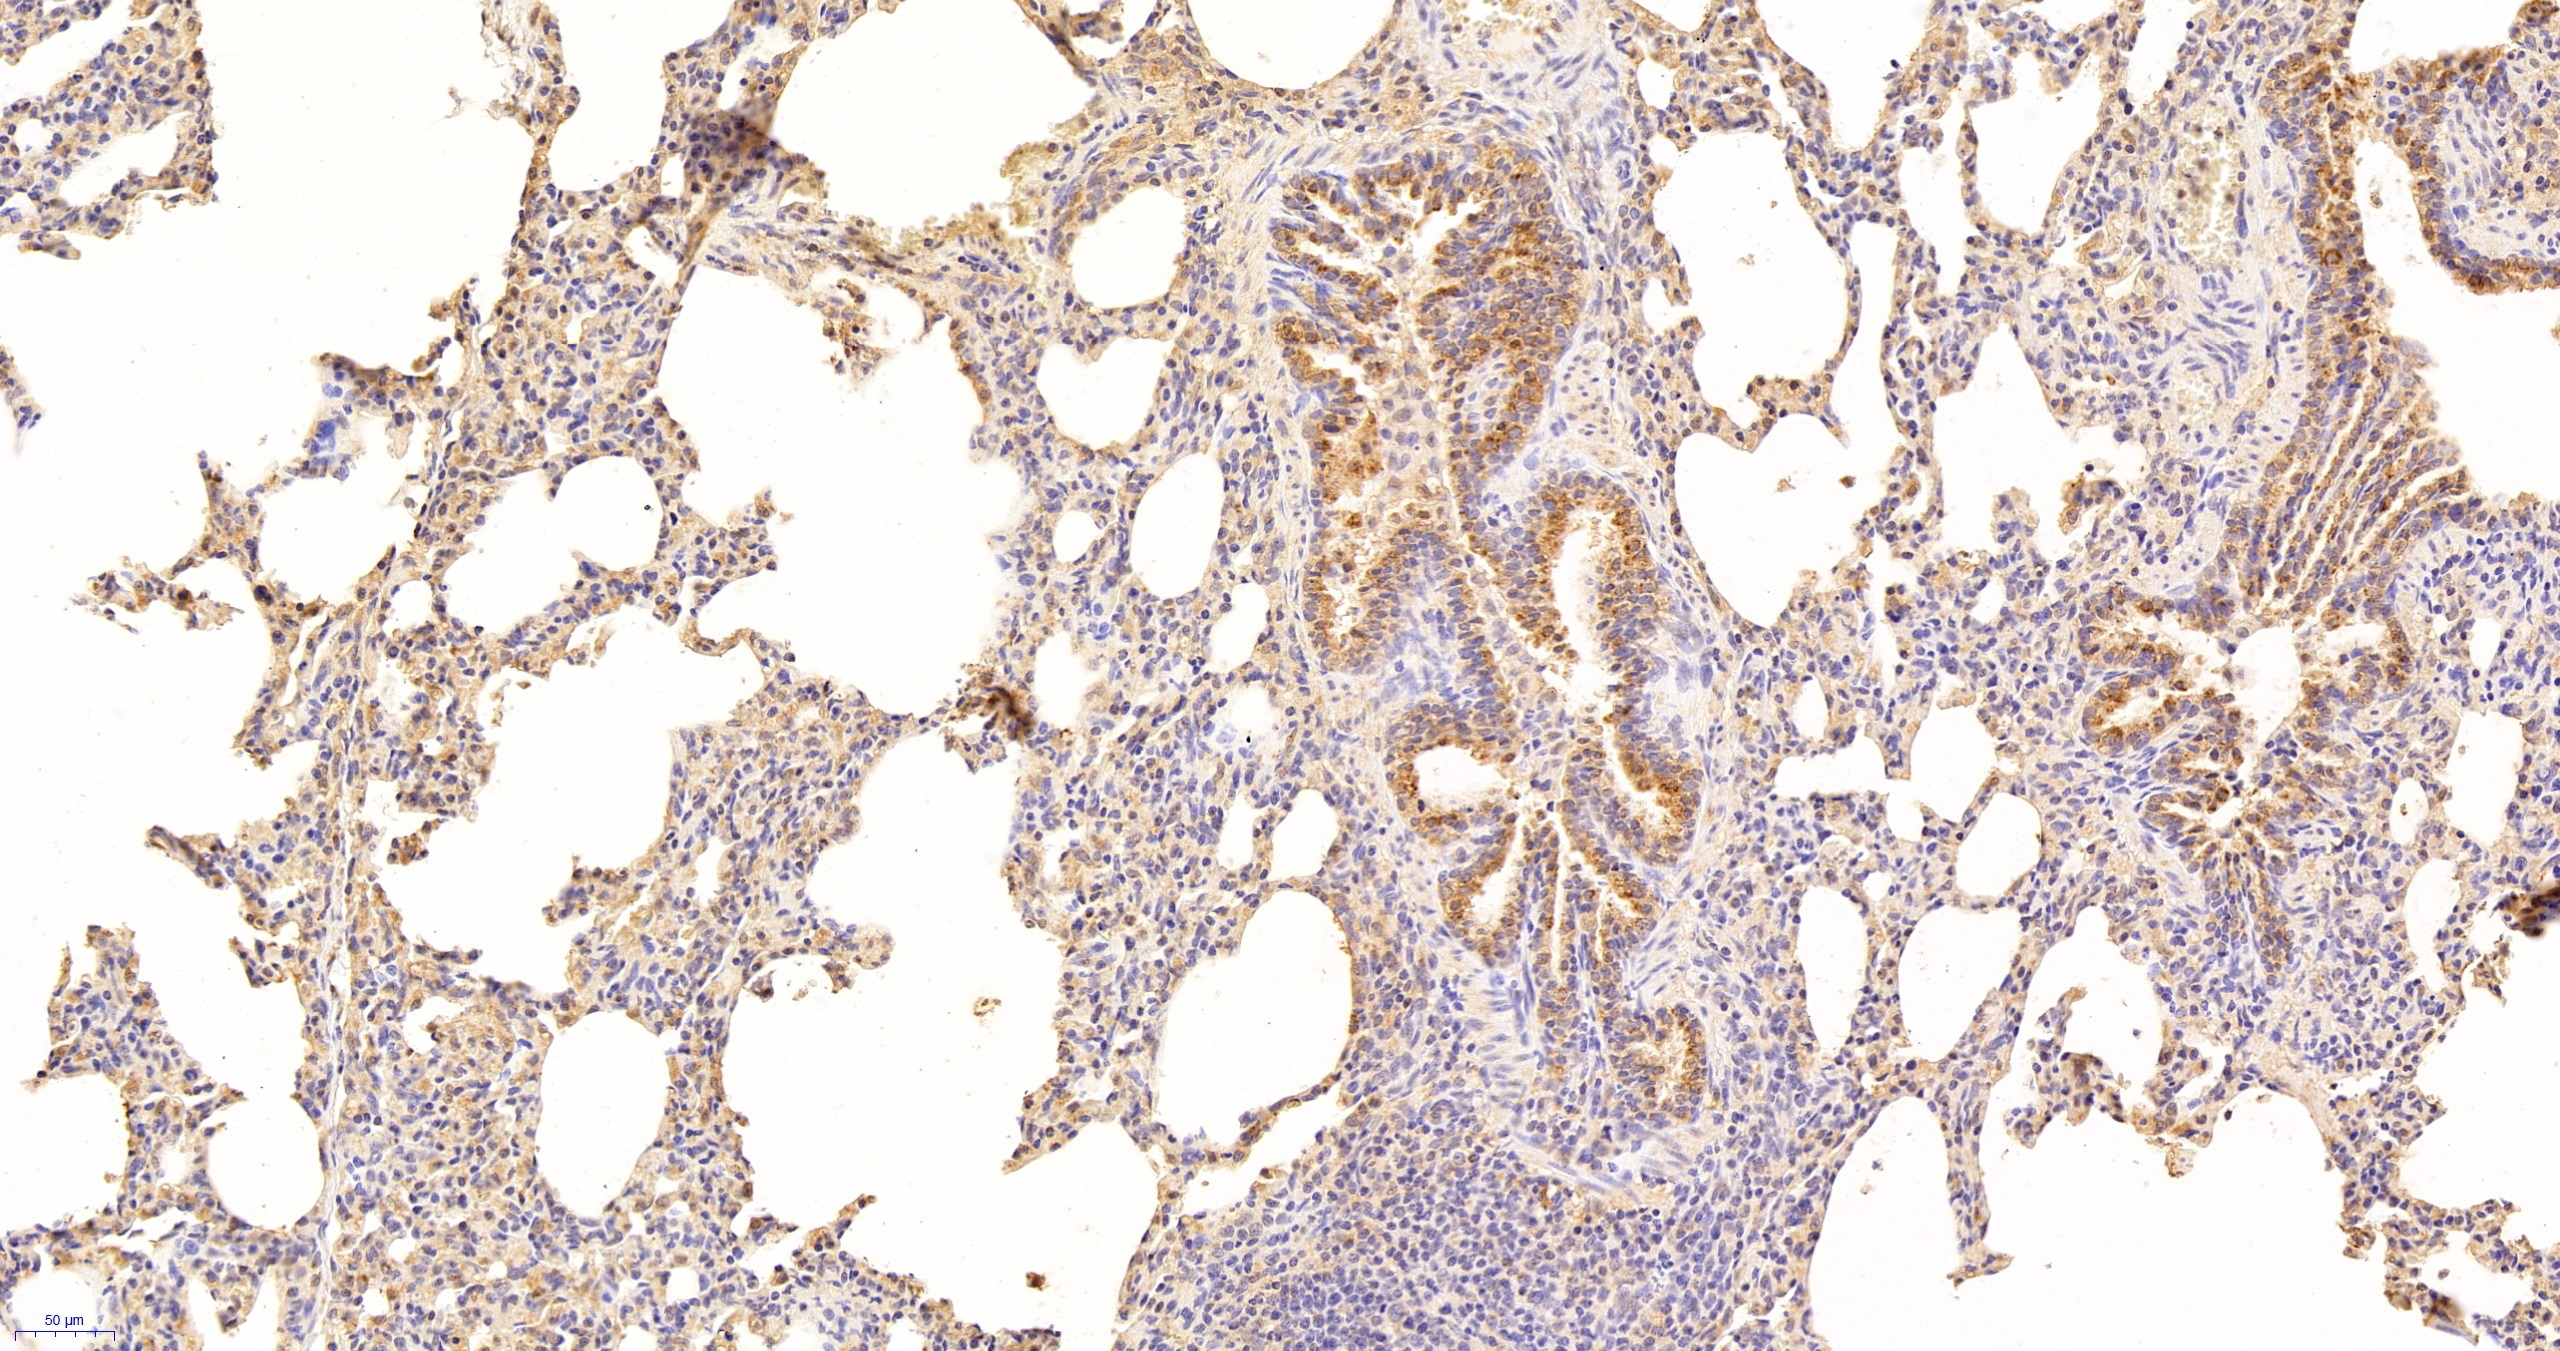

Использование высококачественных первичных антител является неотъемлемым условием получения точных и воспроизводимых результатов в современных научных исследованиях. Например, в рамках онкологического исследования удалось достоверно идентифицировать экспрессию белка PD-L1, что сыграло ключевую роль в оценке потенциальной эффективности иммунотерапии. Применение надежных антител обеспечило стабильность сигнала и высокую специфичность детекции, что позволило получить данные, пригодные для публикации в рецензируемых научных изданиях.